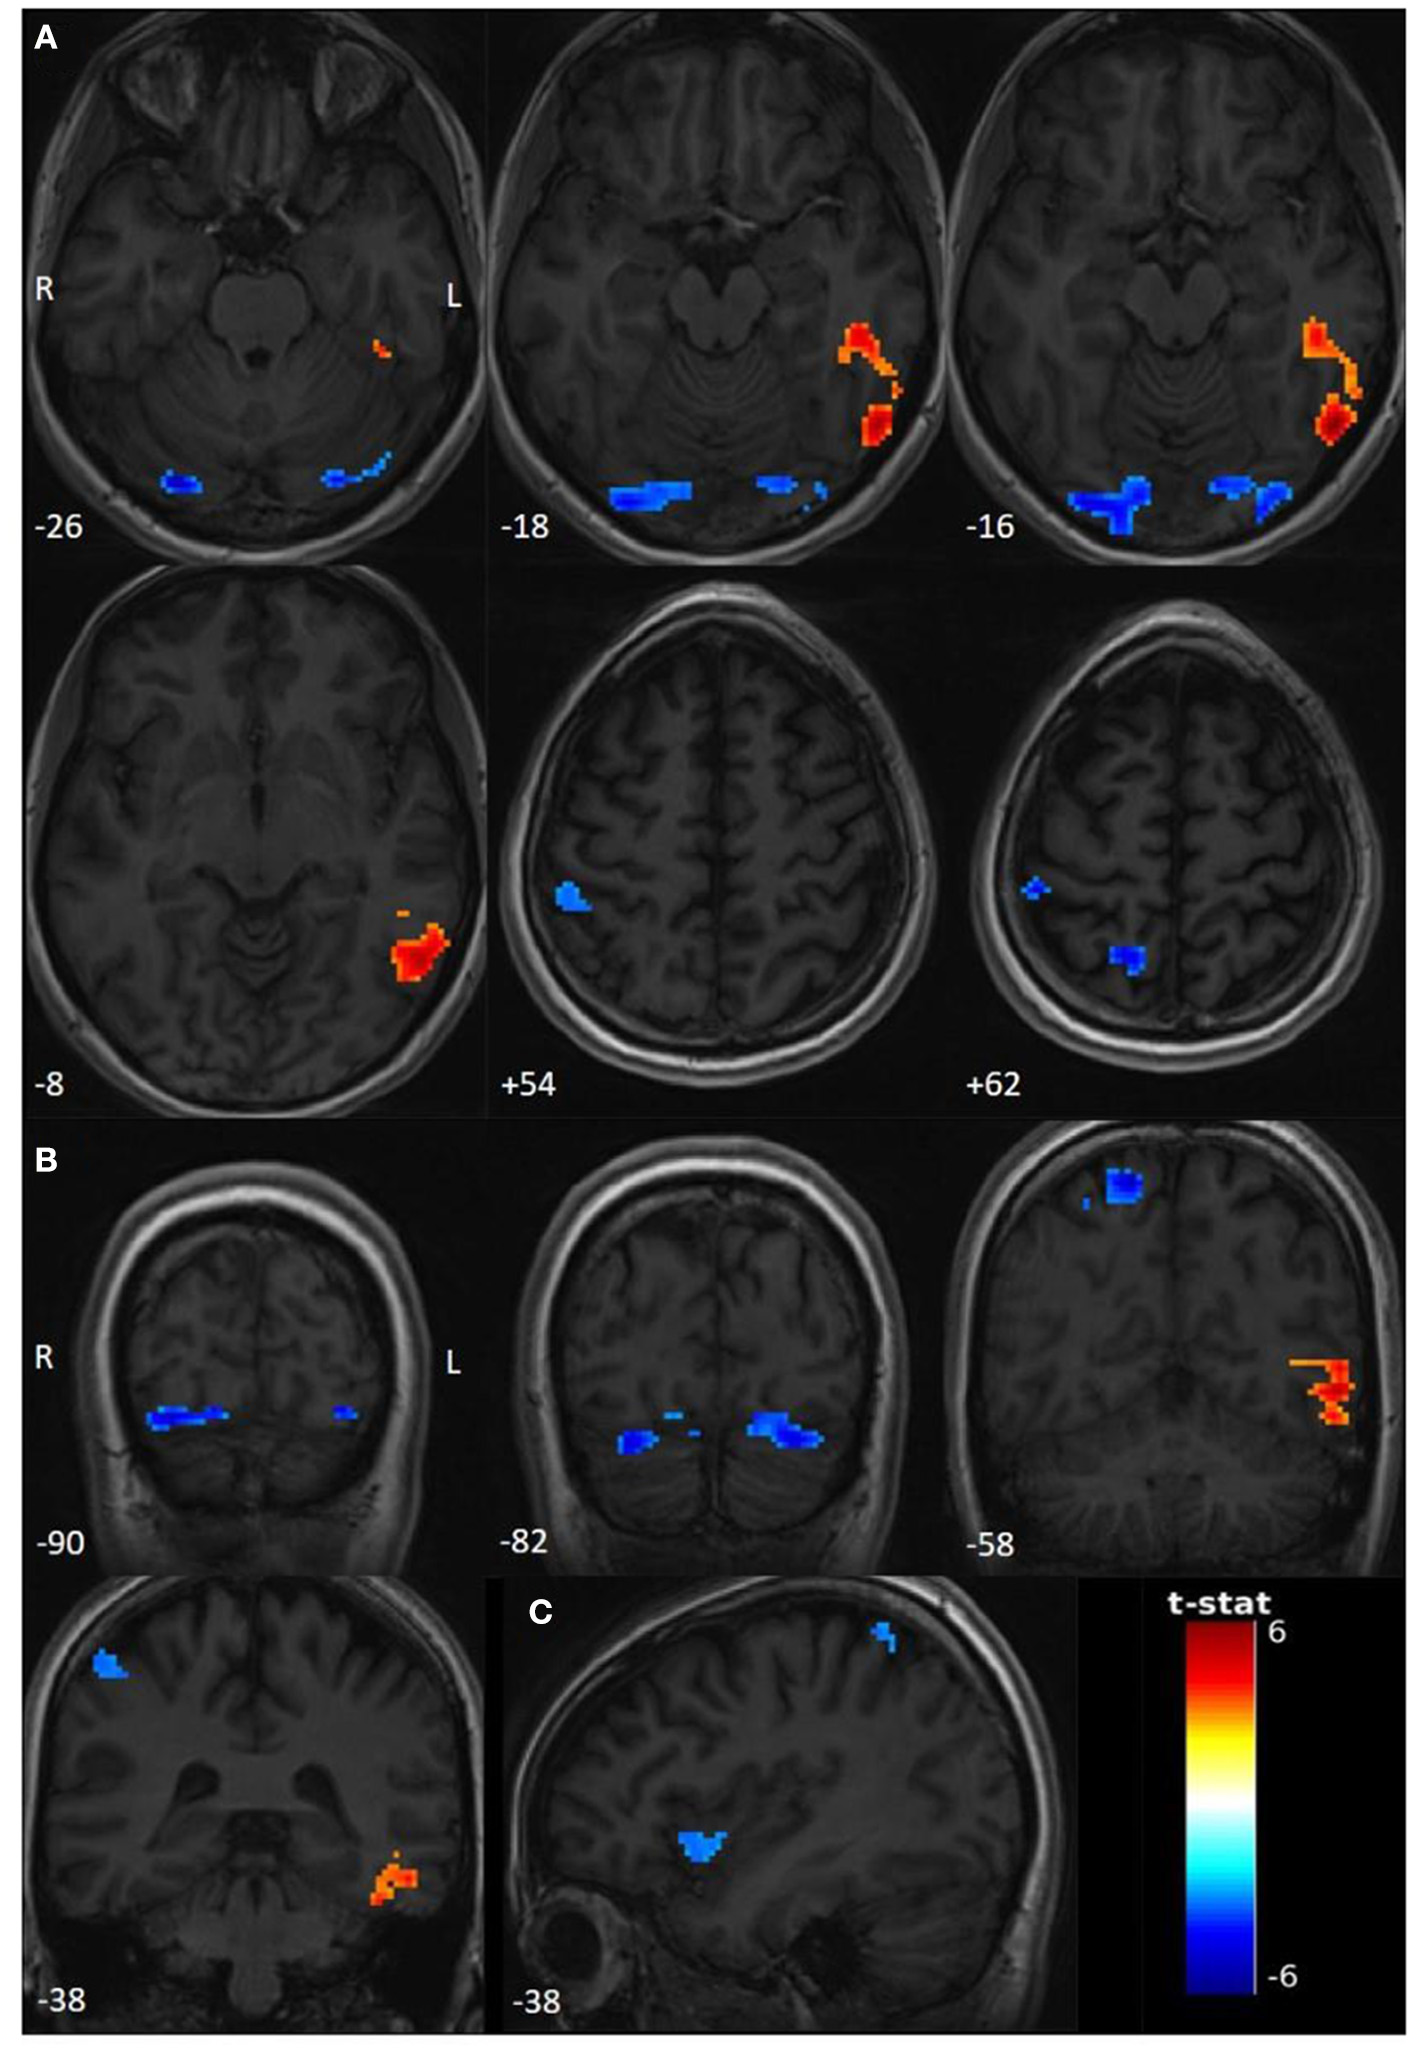

Compared to the rest period, we found significant activations (T > 3.1595, p < 0.001) in the left inferior temporal gyrus (ITG) and the left temporo-occipital junction (TOJ) during the seizure period. Deactivations involved the right precuneus, the right superior parietal lobule (SPL), and the right postcentral gyrus (PoG), bilateral lingual gyri, bilateral inferior occipital gyri (IOG), and bilateral cerebellar lobule (Crus 1). Interestingly, using a sub-threshold analysis (T > 3.1; p < 0.001), we observed an additional deactivation in the anterior right insula (Figure 1, Table 1).

Figure 1

Functional activations and deactivations during contrast PNES > rest (p uncorr < 0.001; cluster-level FWE p < 0.05; neuroradiological convention). The numbers on the bottom left correspond to the MNI coordinates [(A) Z coordinate, (B) Y coordinate, and (C) X coordinate]. The letters L and R correspond respectively to the left and right sides. The palette in warm tones corresponds to activations and the one in cold tones to deactivations. The color bar corresponds to T-scores. (A) Significant activations and deactivations for T > 3.1595, axial slices. (B) Significant activations and deactivations for T > 3.1595, coronal slices. (C) Sub-thresholded deactivations of right insula for T > 3.1.